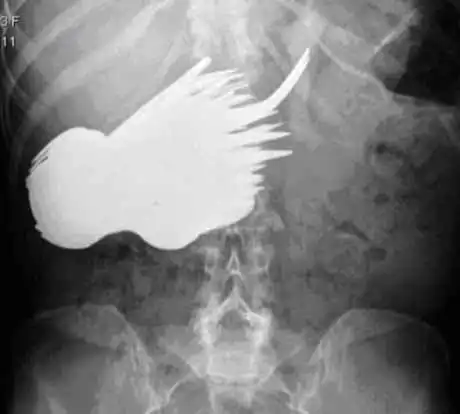

Жительница Голландии Margaret Daalman в возрасте 52 лет почувствовала недомогание в области живота. Результаты рентгеновского обследования ввели врачей в шок. А вот что было у нее извлечено из организма в результате операции ...

Итог: было извлечено 72 металлических вилок и ложек